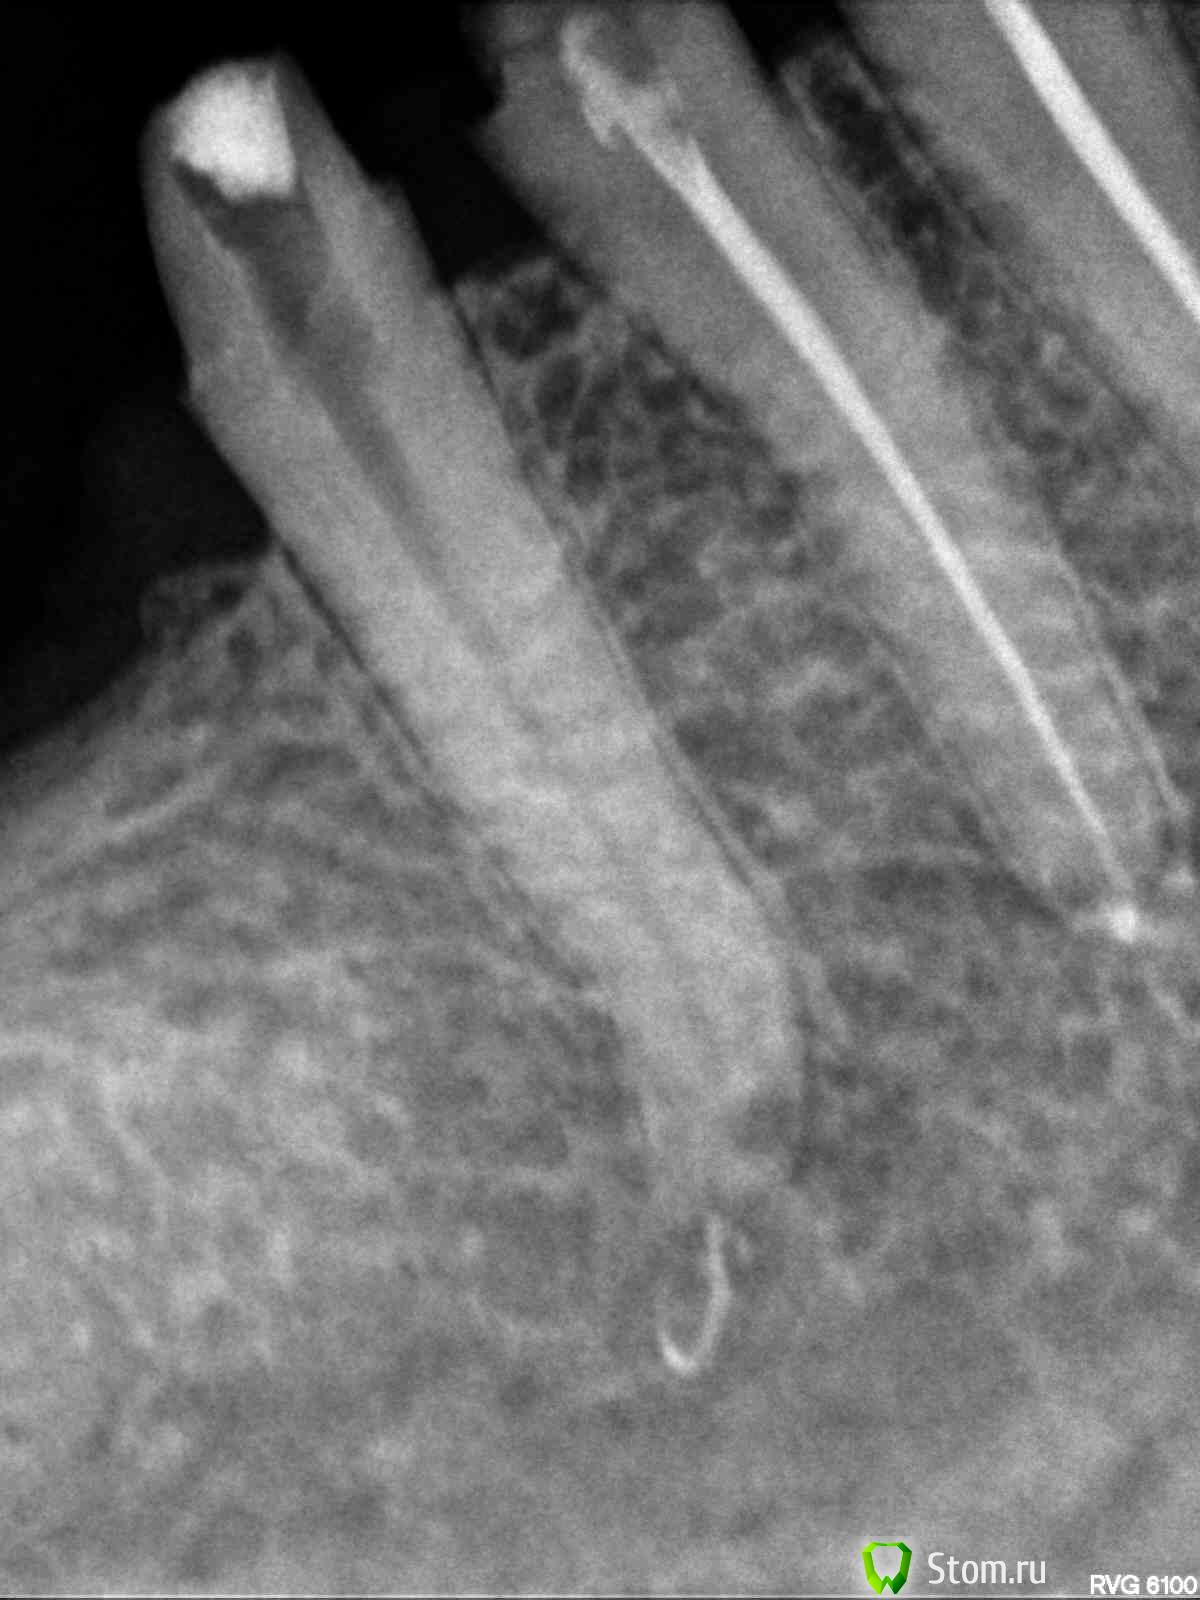

evm Опубликовано 26 апреля, 2012 Поделиться Опубликовано 26 апреля, 2012 Здравствуйте! Проблема: на живых 3-ке, 4-ке и 5-ке внизу справа стояла металлопластмасса (мост полуразрушенный, травмировал десну). Хотела менять осенью, но, поскольку стали появляться ночные ноющие боли (терпимые, но с Метрогилом-Дента), решила не тянуть. 28 марта под анестезией депульпировали все три зуба и запломбировали. Когда пломбировали, в 5-ке чувствовала боль и потом было больно по ней стучать. 10 апреля должна была уже начать протезирование (металлокер. на штифтах). 3 и 4 молчали, а 5-ка все время мозжила и к 10 апреля поддала жару- воспалился лимфоузел и боль усилилась, а также появился болезненный участок рядом с корнем. Канал открыли, положили лекарство под временную пломбу, через три дня - повторили. Терапевт все время убеждала, что с зубом полный порядок. Другой врач сказала: или аллергия, или периодонтит на маленьком учаске (в узкой щели), где тяжело достать (это мой вольный пересказ ее слов). Боль если и утихала, то очень медленно и зуб чувствовала всегда. Через три с половиной недели (22 апреля) взбесилась 4-ка, больно было толкать языком и болела больше, чем 5 (возможно, из-за замерзших накануне ног). Поскольку первый врач считал, что у меня все вылечено, пошла ко второму. Та сделала укол (антибиотик плюс ультракаин, на лидокаин была раньше алергия - крапивница по всему лицу, как герпес), вспомнили мы про физлечение, и в своей поликлинике стала делать дэнос и атерм.УВЧ. Опять пошла алергия, сначала думала - на инъекцию, а теперь думаю, может быть и на ток - пузыри кучно в месте контакта с электродом, а на лидокаин до этого - по всему лицу. Пока все отменили. Зубы периодически о себе напоминают. По 4-ке стучать больнее, чем по 5-ке. 4-ку не открывали. Аллергия (тогда почему 3-ка молчит?) или хр.периодонтит? На снимке видно, что у 5-ки пломб.материал вышел за верхушку, но, скорее всего мозжащая (а иногда пульсирующая, но спать дающая) боль не из-за этого? Ссылка на комментарий

Magdalena Опубликовано 29 апреля, 2012 Поделиться Опубликовано 29 апреля, 2012 Если подвела антисептическая обработка каналов, что Вы предлагаете делать мне? Перелечивать не только 5 зуб, но и 4. Видимо, диагностика по снимкам затруднена, пока нет патологии в виде гранулем и кистОбычные прицельные снимки - двухплоскостные, по ним не всегда видно локализацию воспалительного процесса, ход и количество корневых каналов. Поэтому для более точной диагностики существует компьютерная 3Д - томография (трехмерная), на ней зуб можно "покрутить" и посмотреть со всех сторон, а также в поперечном срезе (это помогает определить кол-во и ход каналов). Ссылка на комментарий